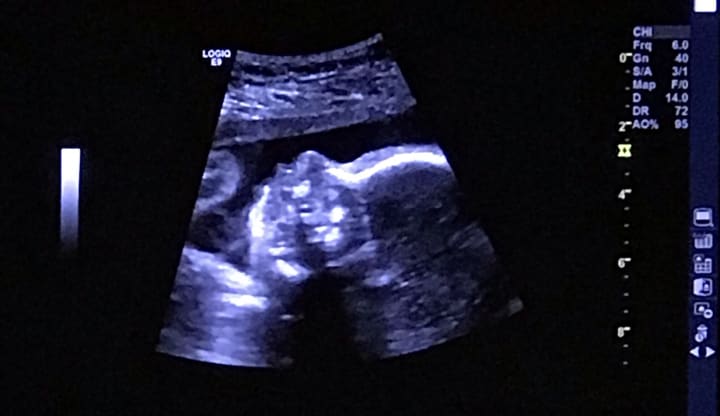

The beginning of my pregnancy was easy, I didn’t have morning sickness or nausea. I craved all of my favorite foods and I could never eat enough! We found out we were having a baby girl at our baby shower and gender reveal on 09/08/18! Exactly one week later, I went into preterm labor which was a terrifying experience. My pregnancy was no longer simple and sweet, it had suddenly become complicated and scary. The doctors stopped my contractions, and I was sent home the next day. I’ve continued to have contractions ever since therefore I’ve been on modified bed rest until my daughter is born.